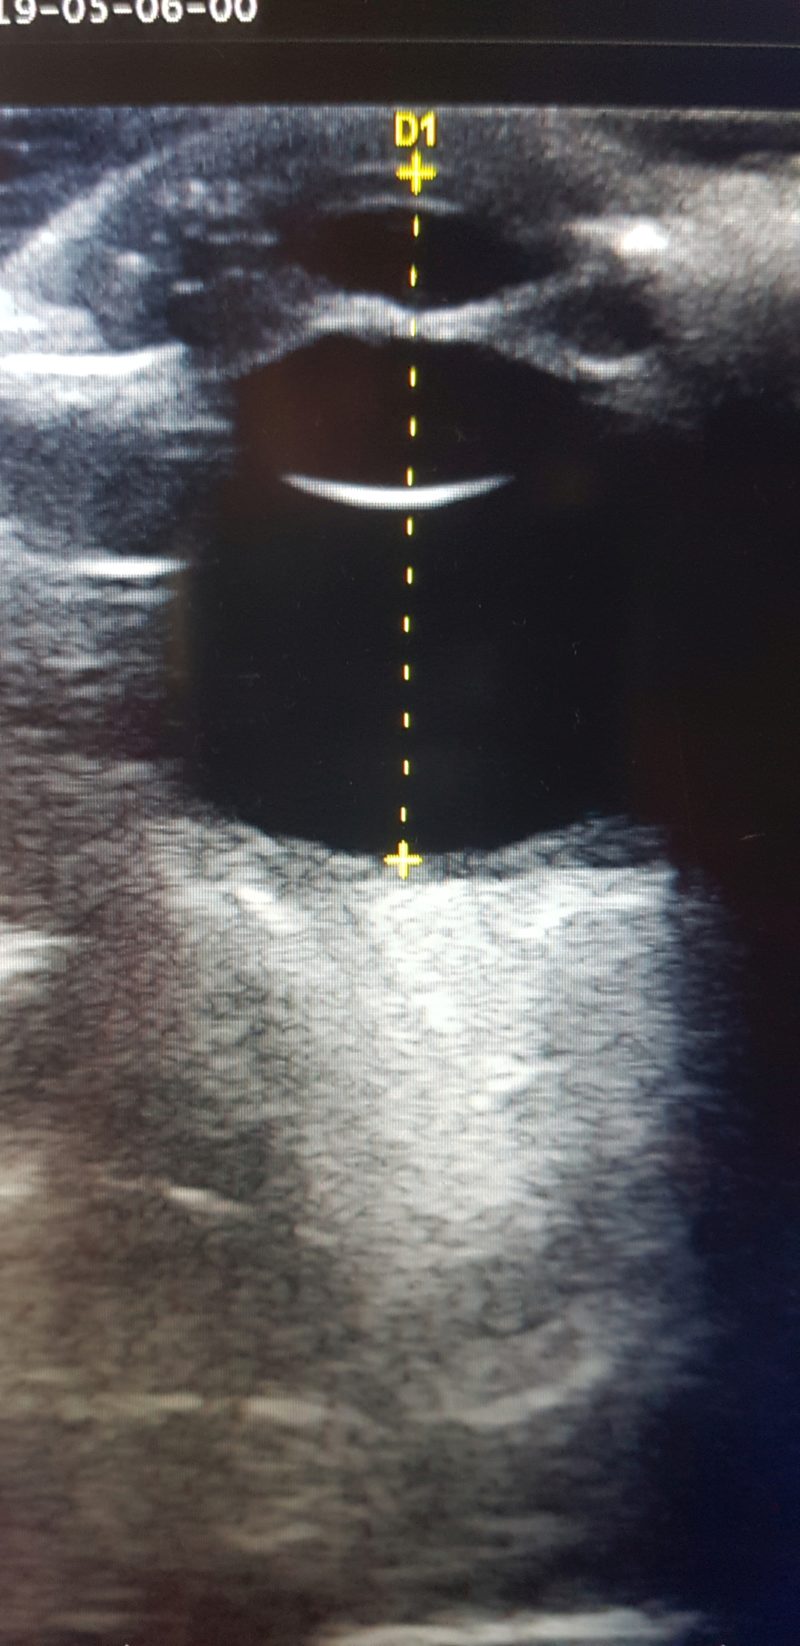

Da das rechte Auge mit der Untersuchungslampe nicht einsehbar war, wurde eine Ultraschalluntersuchung der Augen

durchgeführt. Dies ist gut am wachen Tier unter lokaler Betäubung der Hornhaut mit Augentropfen durchführbar. Im Ultraschall zeigte sich im rechten Auge eine hochgradige Schwellung der Iris, die sich wie ein Napfkuchen in die vordere Augenkammer vorwölbte (Abb. 4).